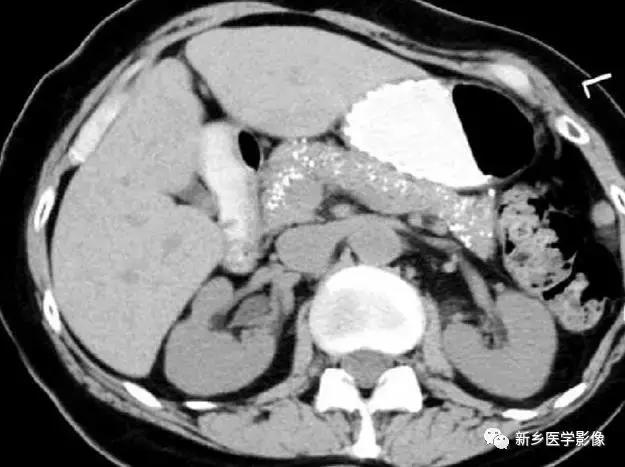

慢性胰腺炎

主要表现为胰腺体积缩小,钙化,有时候假性囊肿囊壁也可钙化。

10

脾和肝肉芽肿

主要表现为点状的钙化,CT显示清晰,腹部平片有时候表现不明显